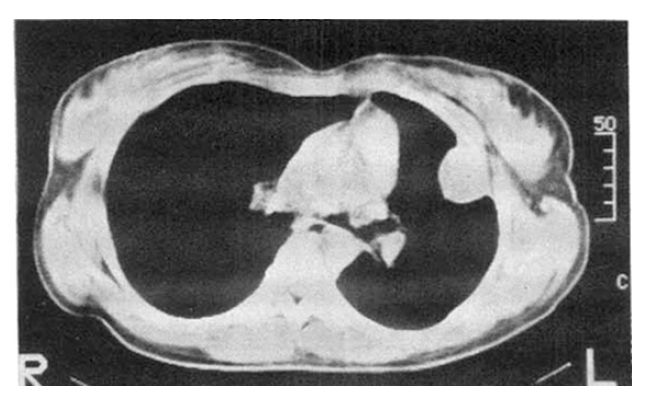

A chest X-ray revealed the shadow of a well-defined marginated mass in the left lung field (Fig. 1). A chest CT scan showed a mass lesion in the left anterolateral thorax broadly abutting the chest wall (Fig. 2). Gastrofiberscopic and colonofiberscopic examinations were normal. An abdominal ultrasonogram was normal. A bone scan was unremarkable. A percutaneous transthoracic biopsy was done. Histologically, the tumor tissue was composed of scattered osteoclastic-type multinucleated giant cells and large pleomorphic mononuclear cells (Fig. 3). The tumor cells showed positive immunostaining for vimentin. Stains for cytokeratin, epithelial membrane antigen were negative.

Fig. 2.

Chest CT: A soft-tissue mass lesion in the anterolateral thorax broadly abutts the chest wall.